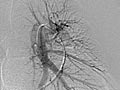

La angiografía pulmonar es una radiografía que utiliza un tinte especial y una cámara (fluoroscopia) para tomar imágenes del flujo sanguíneo en los vasos sanguíneos de los pulmones.

La angiografía pulmonar se usa para evaluar las arterias que van a los pulmones (arterias pulmonares) y los vasos sanguíneos en los pulmones. También puede detectar el estrechamiento o la obstrucción de un vaso sanguíneo que reduce o detiene el flujo de sangre.

La angiografía pulmonar es una radiografía que utiliza un tinte especial y una cámara (fluoroscopia) para tomar imágenes del flujo sanguíneo en los vasos sanguíneos de los pulmones. Es posible que su médico le comunique algunos resultados inmediatamente después de la prueba. Por lo general, los resultados completos están listos el mismo día.

Angiografía pulmonar

Normal:

El material de contraste fluye en forma pareja a través de los vasos sanguíneos.

No se observa estrechamiento, obstrucción, abultamiento ni otro problema en los vasos sanguíneos. Las presiones arteriales pulmonares son normales.

Anormal:

Los vasos sanguíneos que no se encuentran en su posición normal podrían indicar que están siendo empujados por un tumor u otro crecimiento.

Una protuberancia en un vaso sanguíneo podría indicar un debilitamiento de la pared del vaso sanguíneo ( aneurisma).

La pérdida de material de contraste de un vaso sanguíneo podría indicar que hay un orificio en dicho vaso.

Hay un vaso anormal o un bloqueo entre los vasos en el pulmón.

Hay ramificación anormal de los vasos sanguíneos desde el nacimiento (congénita).